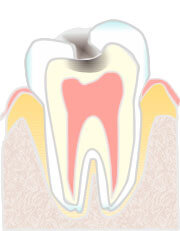

エナメル質内の虫歯

C1:エナメル質内の虫歯

歯の表面のエナメル質が溶け始めた段階の虫歯です。痛みがなく、ついつい放っておきがちです。 虫歯の部分だけを削除して、合成樹脂(レジン)を充填します。